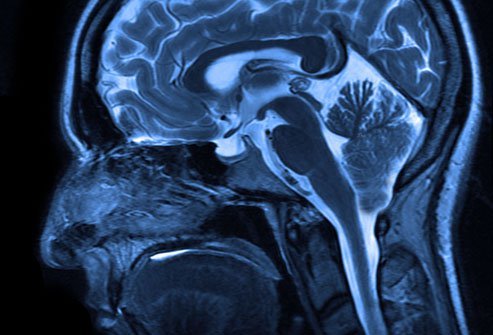

- Chiari malformation or Arnold-Chiari malformation is usually considered a birth defect. It is a condition where part of the brain called the cerebellum protrudes through an opening in the back of the skull and into the spinal canal. It also can be related to where the bones of the spine don't form properly and membranes protrude out of a child's back.

- This condition also puts pressure on the nerves and spinal cord and disrupts the flow of cerebrospinal fluid. The disruption of that flow can cause debilitating pain and other severe symptoms. For many, the malformation exists at birth, but it can go years or even decades without presenting any symptoms. Most people are diagnosed with Chiari during childhood, but some will not be diagnosed until they are adults.